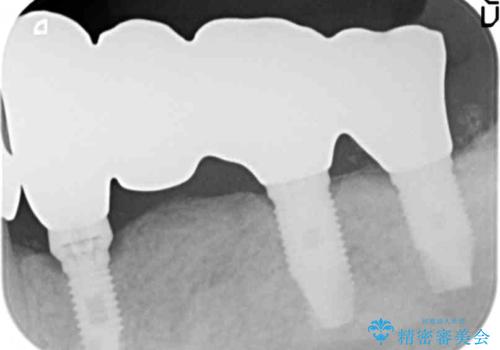

禁煙指導と歯周病治療後、左下臼歯部(左下467埋入)のインプラント治療を行いました。

インプラントの埋入は、抜歯後4ヶ月程度骨の治癒を待ったり、骨が少ない部分に関しては骨増生を行ったりして順次行いました。

- ¥1,287,000 (インプラント×3本、骨増生、土台×3本、仮歯×4本、クラウン×4本) ※税込費用は治療当時の料金となります

インプラントの種類:スプラインツイスト(HAコーティング)

固定様式:スクリュー固定

クラウンの種類:ベレッツァクラウン